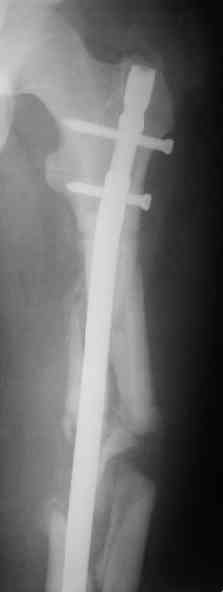

> денамизация - февраль 2006. ( 3 и 4 снимки) на сегодняшний день (снимок 5) беспокоит боли в тбс...

Однозначно: удалить, рассверлить, перештифтовать более толстым гвоздем. ЭТОТ 9 мм будет? Возьмите 12-14.

Дистально обязательно два винта! Проксимально можно один динамический. Больной будет счастлив на следующий же день!

Учитывая точку введения - верхушка б\вертела - что бы исправить варус взял бы соответствующий гвоздь: длинную Гамму или PFN или Recon

Судя по уровню перелома, винты в шейку избыточны, подойдет и диафизарный гвоздь. Все, что нужно, это тиски и труба. Загнуть сразу ниже отверстий градусов на 8-10, и вся недолга. Последние годы у нас это рутинная практика. Предызогнутые еще с завода гвозди неудобны тем, что они уже правый-левый.

Согласен, что закрытый реостеосинтез с рассверливанием и коррекцией оси - это то, что надо. Мы бы ввели в центральный отломок статических 2-3 винта, и один динамический винт в дистальном отломке.